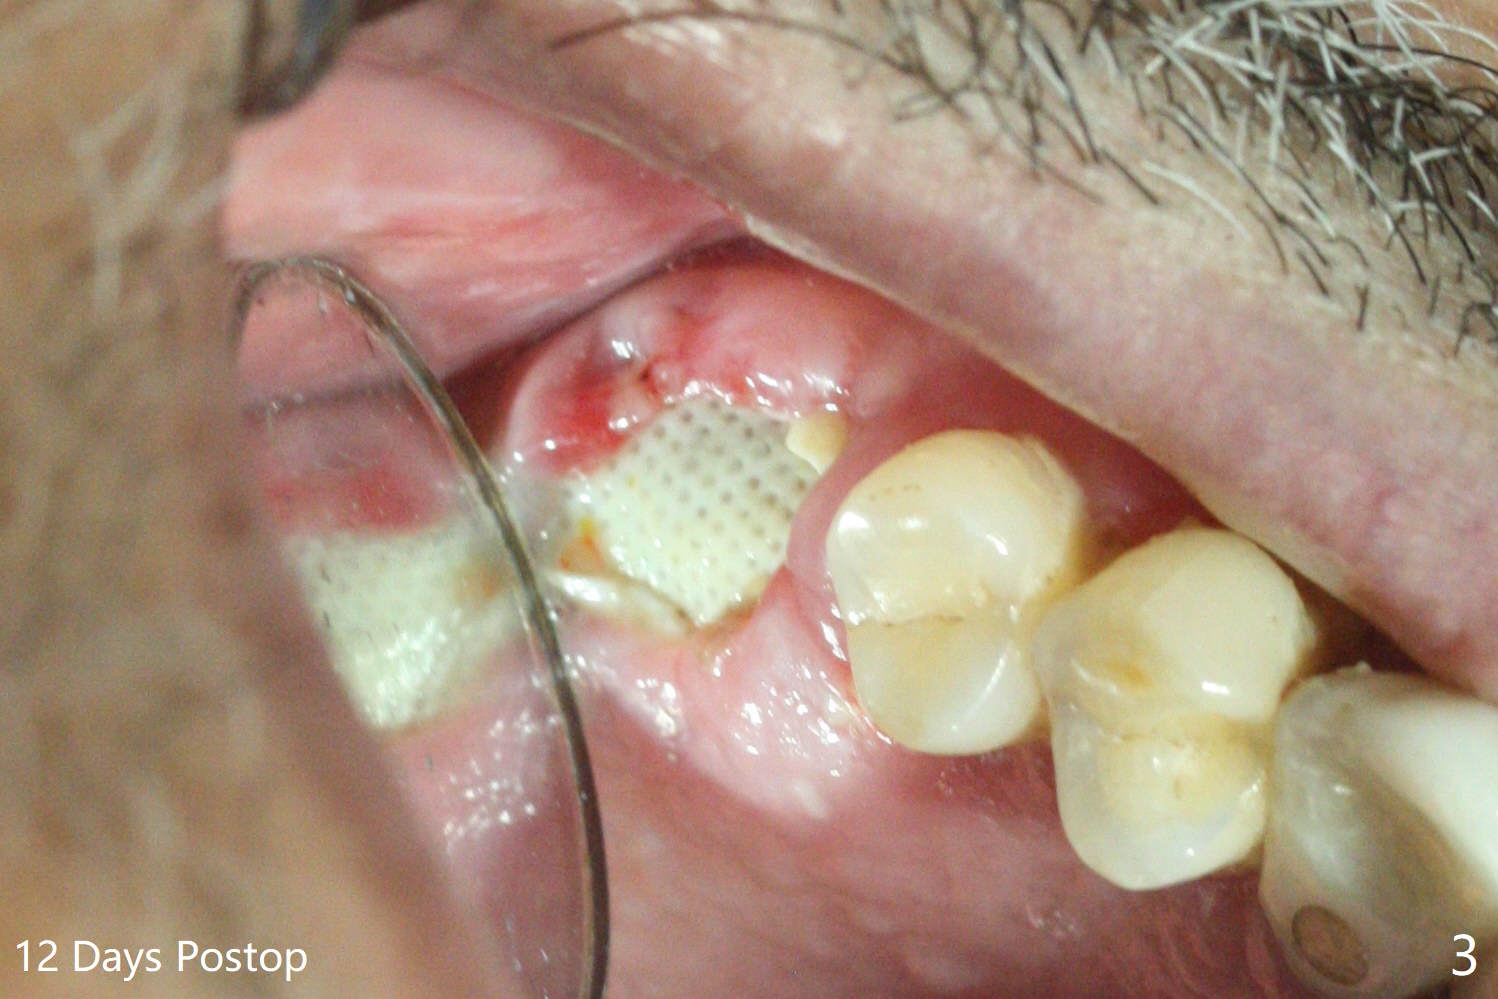

66岁男要求拔除2号牙(近中倾斜,3号牙缺失,图一),术中发现巨大骨质缺损,病人同意植骨(皮质骨,用血调袢,图二:*),覆盖Cytoplast,使用PTFE缝线,8字形缝合,两次。之后牙周敷料覆盖。术后十二天,敷料松动,但是不脱落,因为敷料与缝线粘连,牙龈好像已经固定不可吸收膜,不得不撤除缝线(图三)。Return to Protect Graft 下一个不使用敷料病例 位点保存 Xin Wei, DDS, PhD, MS 1st edition 06/12/2021, last revision 07/03/2021